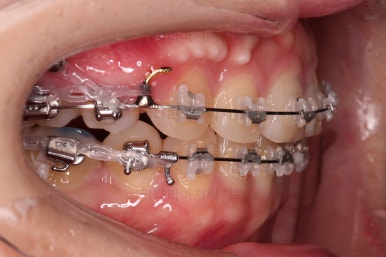

마찬가지로 부산연산동교정치과 초진 시 입안의 모습입니다.

눈에 띄는 것은 윗니 안쪽 치아 하나가 아예 입천장쪽으로 나서 매우 삐뚤어요.

저렇게 삼각혁으로 배치되어 있는 치아는 셋 중 하나는 꼭 썩어요.

셋 사이에 음식물이 잘 끼고 양치가 힘들기 때문이죠.

아래 앞니도 삐뚤한 편이었고 아래 앞니가 불쑥 위로 올라와 있어서 이를 악 다물면 위아래 앞니가 많이 겹치는 "과개교합" 패턴이 나타나요.

윗니가 전반적으로 아랫니보다 앞에 나와 있어서 2급 부정교합에 윗니만 튀어나온 양상이고 이 때문에 윗니 앞니가 다치고 부러졌따가 떼운 흔적이 보이네요.

교정장치를 부착한 직후의 모습인데요.

눈에 보이는 장치의 모습과 입매의 변화를 참고해 주세요.

옆라인만 비교해보면요.

입매가 거의 변하지 않는 타입이세요.

교정장치 때문에 입이 많이 나올지, 안나올지는 사람마다 매우 달라서 말그대로 붙여봐야 아는 경우가 많습니다.

치아를 뽑은 위치, 당겨야 할 정도가 달라 미니스크류를 몇 개 사용했어요.

미니스크류는 앞뒤조절, 높낮이 조절, 각도 조절, 안밖의 위치조절 등 난이도 높은 치료를 가능하게 해준답니다.